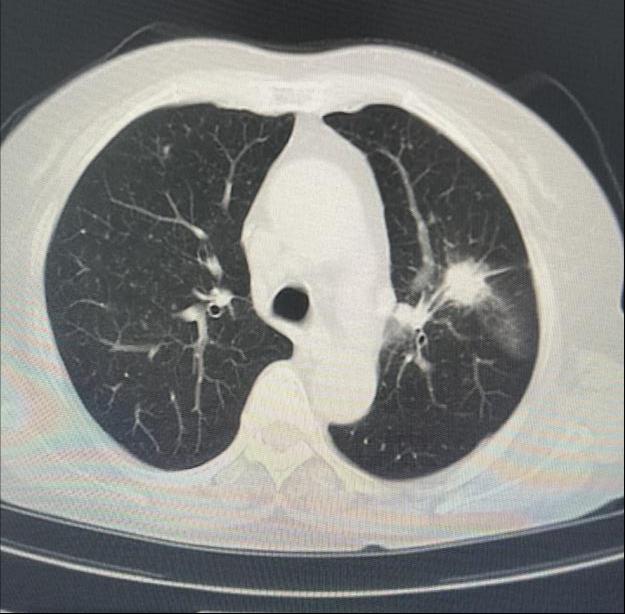

患者女性,因“气短1月”来门诊就诊,为明确诊断进一步治疗,收入MILAN.COM。入院后完善相关检查,胸部CT示左肺上叶前段高密度灶,与家属充分沟通后,决定为患者行超声支气管镜检查。主任医师吴水淼与主管护师薛冬冬为患者行气管镜检查,镜下示:双肺支气管均未见明显异常,结合CT给予超声探查,于左肺上叶前段亚支探及偏心异常回声区,由于亚支位置较高且管腔较窄,活检钳无法到达,给予冷冻肺活检。此次检查过程顺利,成功获取2块活检标本,活检病理结果提示为粘液腺癌。